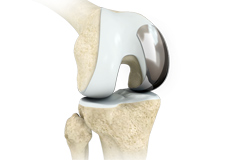

Total Knee Replacement

Total knee replacement, also called total knee arthroplasty, is a surgical procedure in which the worn out or damaged surfaces of the knee joint is removed and replaced with an artificial prosthesis.

Knee Implants

Knee implants are artificial devices that form the essential parts of the knee during a knee replacement surgery. The knee implants vary by size, shape, and material. Implants are made of biocompatible materials that are accepted by the body without producing any rejection response. Implants can be made of metal alloys, ceramic or plastic, and can be joined to the bone.